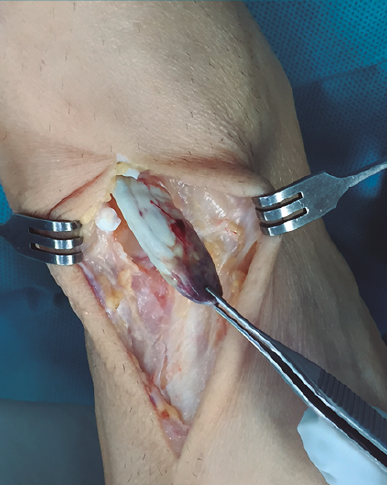

Figura 1. Vaina del tendón tibial anterior con muñón ascendido proximalmente que se transparenta por debajo del retinaculum superior.

Con el paciente en decúbito supino y con isquemia a nivel del muslo, se realiza una incisión cutánea longitudinal anterior al nivel del trayecto del TA, extendiéndola al nivel del mediopié sobre la articulación astrágalo-escafo-cuneana (Figura 1).

Figura 2. Tendón tibial anterior rescatado tras apertura del retinaculum superior.

Se prosigue con una disección de partes blandas, identificando y protegiendo las terminaciones nerviosas superficiales hasta llegar al retinaculum extensor, realizando apertura del mismo hasta encontrar el muñón proximal ascendido del TA (Figura 2). En los casos evolucionados o crónicos se puede apreciar una fibrosis que ocupa el compartimento del TA.